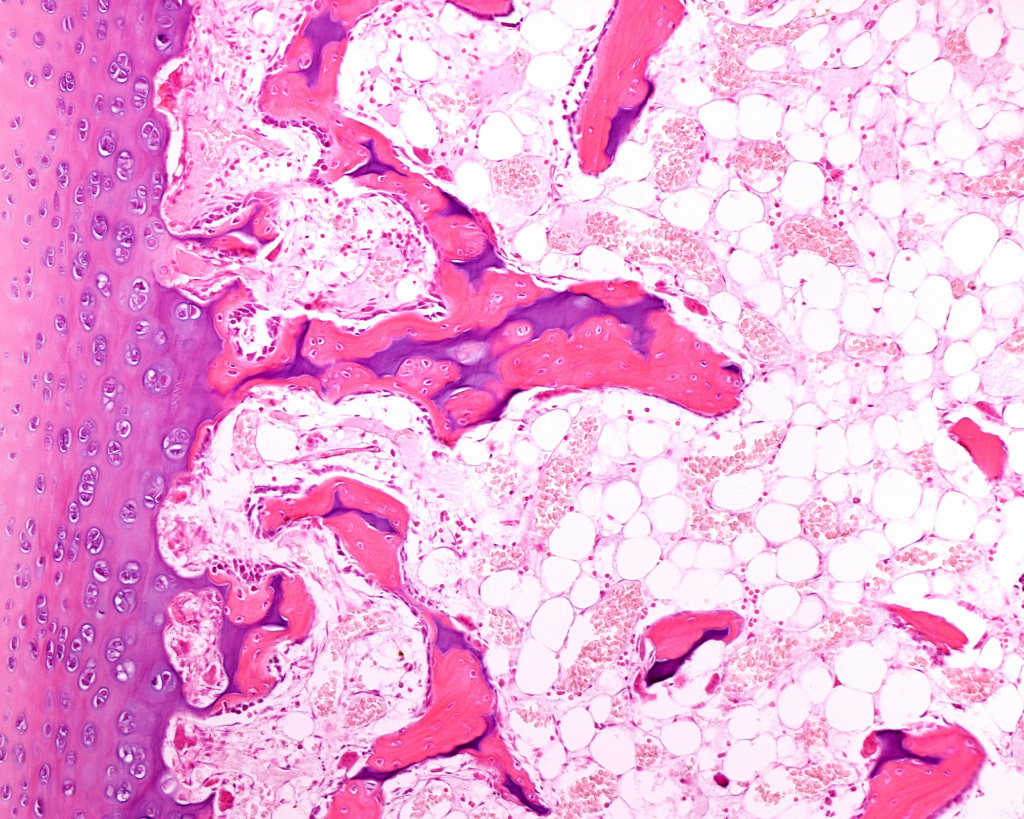

Our medical studies confirmed our interest in histology.